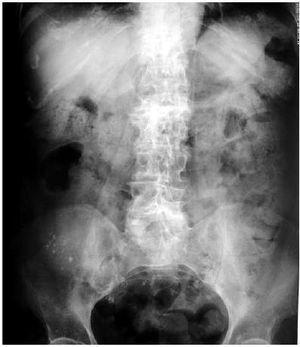

Mujer de 62 años en hemodiálsis crónica desde hace 6 años, con Diabetes Mellitus, hiperparatiroidismo secundario e hipertensión arterial como antecedentes personales más importantes. Consulta por sensación de plenitud abdominal, estreñimiento y nauseas. La exploración física y resultados analíticos fueron irrelevantes, destacando en la radiografía simple de abdomen material radio-opaco, disperso por todo el recorrido del colon, recordando una imagen de cielo estrellado. Revisando el tratamiento, se observó que desde hacía cuatro meses estaba tomando Carbonato de Lantano. Inicialmente asociado a otros quelantes del fósforo. La paciente no había recibido ningún tipo de contraste en los últimos 6 meses. Tras la retirada del Carbonato de Lantano y tratamiento con laxantes, la sintomatología desapareció y en la radiografía de abdomen realizada 3 semanas después apenas se apreciaba material radio-opaco.

Figura 1. Radiografía de abdomen en vacío inicial